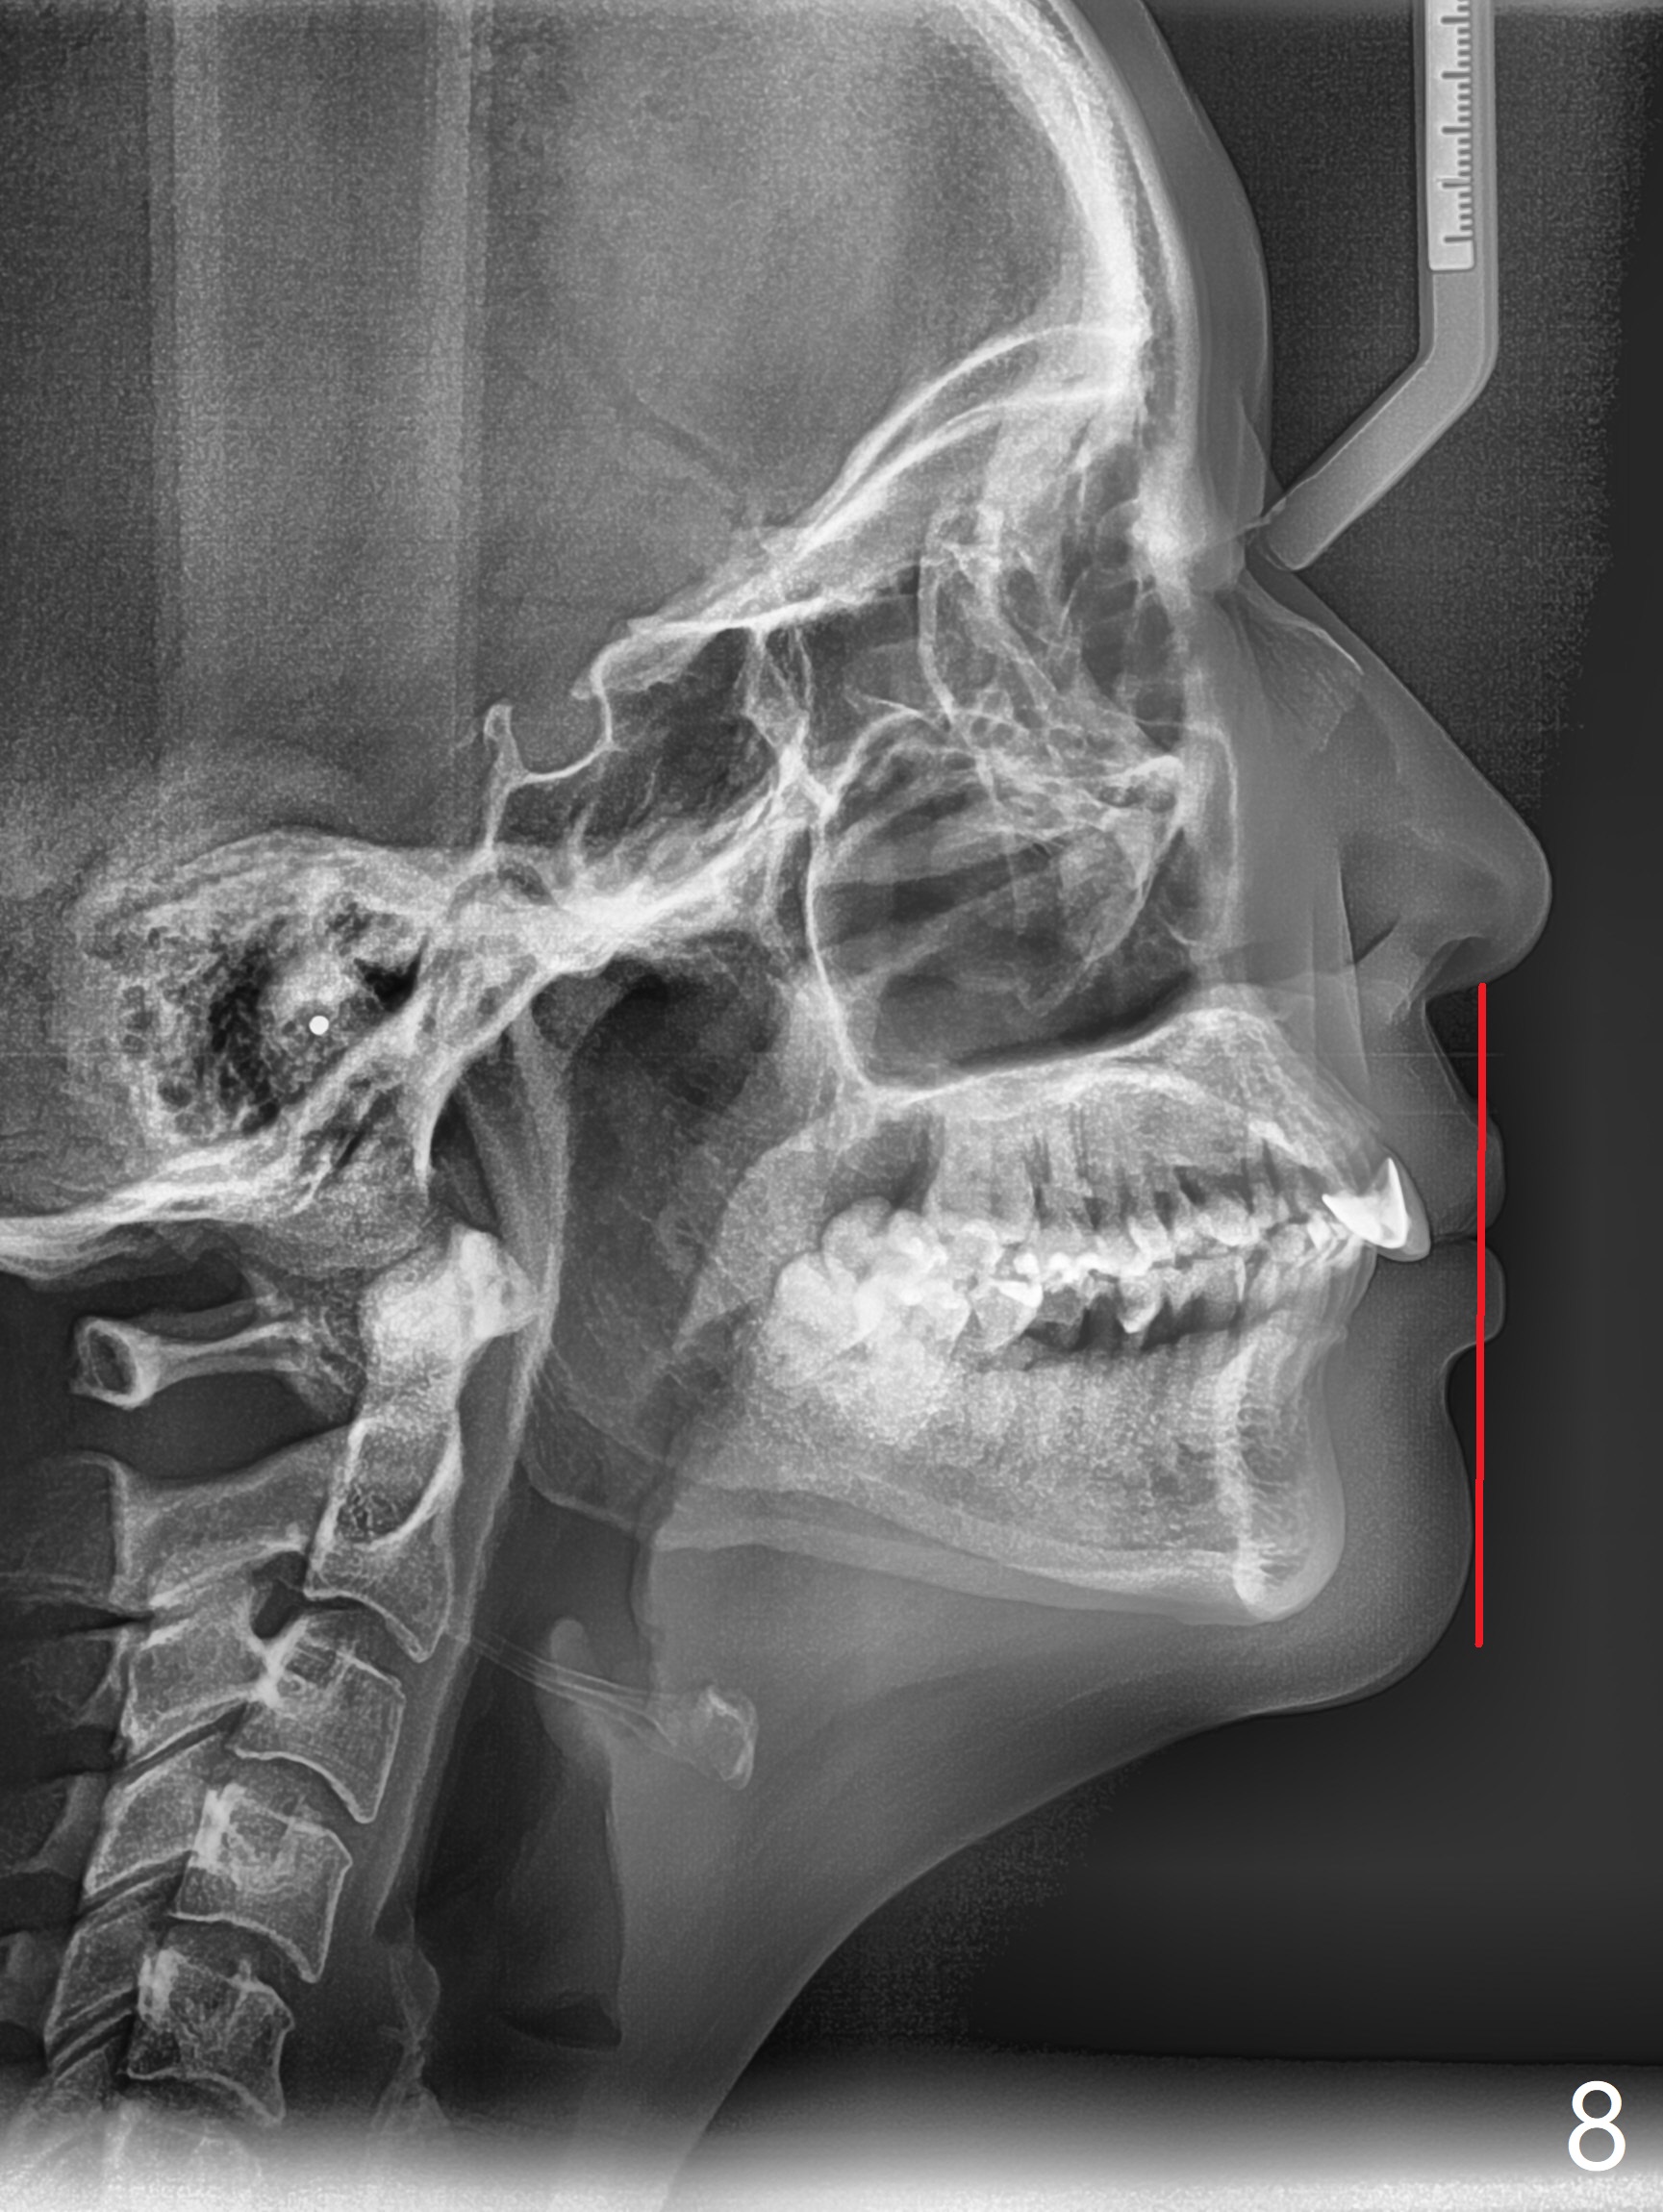

31岁女,牙周炎,安格氏二类错𬌗(图一至八),深洗后,同意牙齿矫正,但是要求保留左下智齿,前移7,8,取代6,左上6过度萌出(图三:箭头)。

初步计划:第一期安置矫正器,排列,建立正常前牙覆合覆盖,二类牵拉。尽量竖直左下7,8(图十一:白色轮廓);使用两个微型植体(图九:黑线(两个植体之间放置power chain(红线)))压入左上6(图十(圆圈:近中微型植体),与图三对比),为左下7近中移位(红色箭头)创造空间。

第二期在左下4和5之间植入微型植体作为支抗(图十一:红色),利用7远中长勾(粉红色)和橡皮筋,先让7平行近中移位,控制根torque。A 31-year-old woman with Class II Division I malocclusion requests orthodontic treatment without extraction of LL8. U8s and LL6 have been extracted with SRP. The 1st stage will be alignment , intrusion of UL6, upright of LL7 and 8 and correction of Class II malocclusion using double twin.